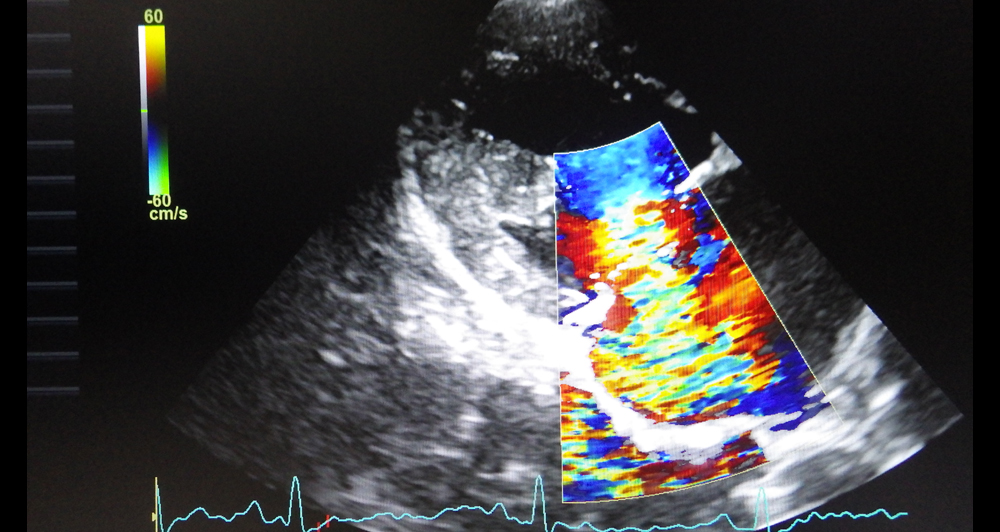

心臓の中では血液は一方通行で流れています。そのために心臓の各部屋の間には弁がついており、その一つが僧帽弁です。

加齢にともない弁やそれを支える腱索が変性し、痛んでくるため、弁がちゃんと閉じなくなってきて起こります。

心臓の中の血液の逆流量が少ない場合は無症状ですが、逆流量が多くなると運動不耐性や発咳などの症状が現れます。